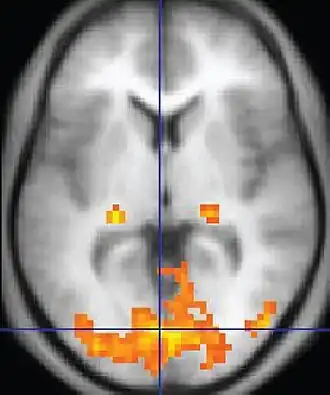

Functional MRI (fMRI) Blood-oxygen-level dependent imaging BOLD Changes in oxygen saturation-dependent magnetism of hemoglobin reflects tissue activity.[78] Localizing brain activity from performing an assigned task (e.g. talking, moving fingers) before surgery, also used in research of cognition.[79]

Perfusion weighted (PWI) Dynamic susceptibility contrast DSC Measures changes over time in susceptibility-induced signal loss due to gadolinium contrast injection.[72]